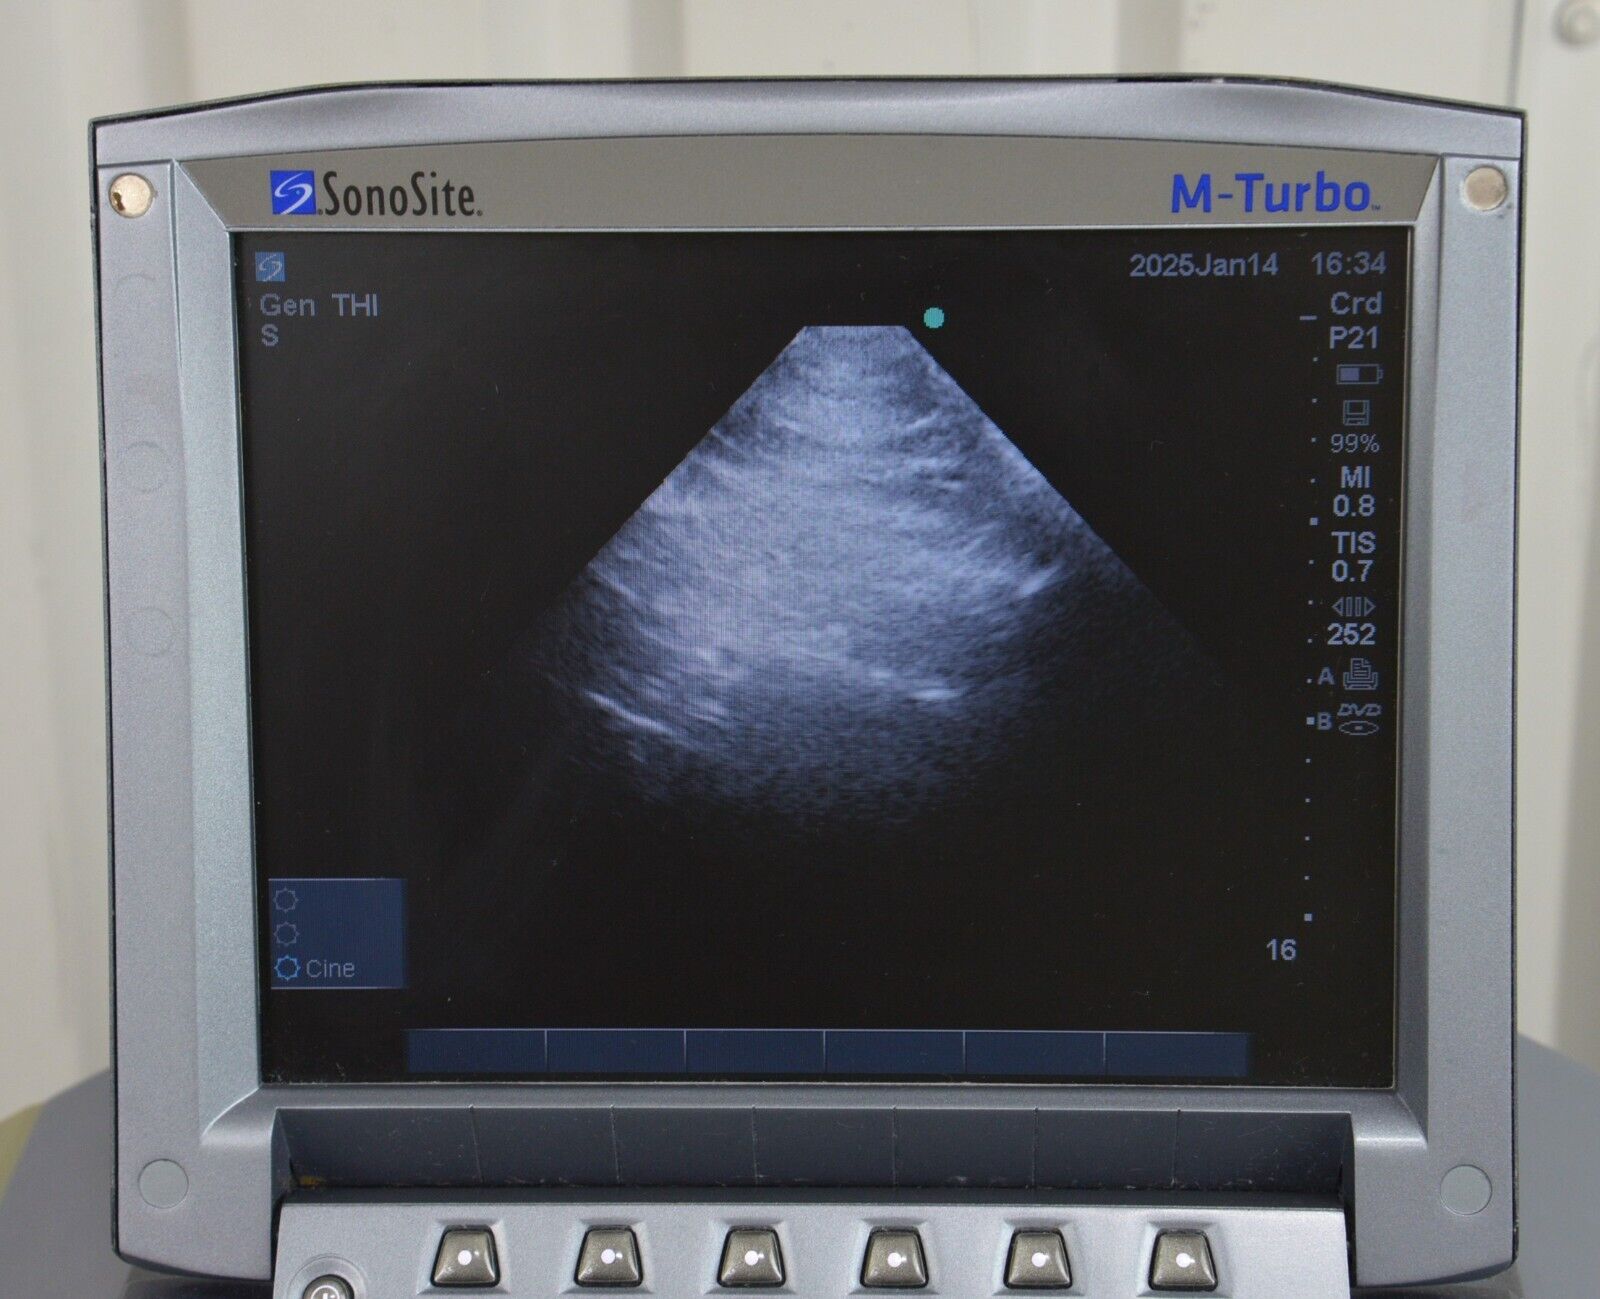

- Fujifilm Sonosite M-Turbo Ultrasound System W/ SonoSite P21x/5-1 MHz Transducer

January 15, 2025Fujifilm Sonosite M-Turbo Ultrasound System W/ SonoSite P21x/5-1 MHz Transducer

Fujifilm Sonosite M-Turbo Ultrasound System W/ SonoSite P21x/5-1 MHz Transducer

This Fujifilm Sonosite M-Turbo Ultrasound System W/ SonoSite P21x/5-1 MHz Transducer is in good working condition. This unit powers on properly and the display screen produces a clear picture. The buttons respond properly to selection and the connections are clean and in good condition. The battery holds a charge. There are a few minor scuff marks from previous use (see photos). This item comes with a 30 day satisfaction guarantee. Includes everything displayed in the photos and nothing else.